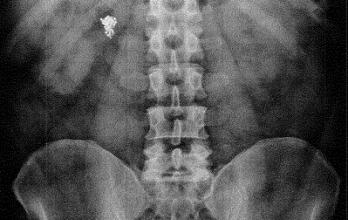

El médico Patricio Castillo analizó la radiografía en la que se muestra que el objeto permanece en el interior del intestino del sospechoso. Considera que, por el momento, no existe obstrucción. Por ende, según él, se puede evacuar.

Sin embargo, el experto enfatiza que si no se extrae podría presentarse algún tipo de infección. Para sacarla, entonces, tendrían que hacerle una limpieza intestinal y una aspiración nasogástrica. “Luego se debería tratar con medicamentos por el riesgo de infección”.